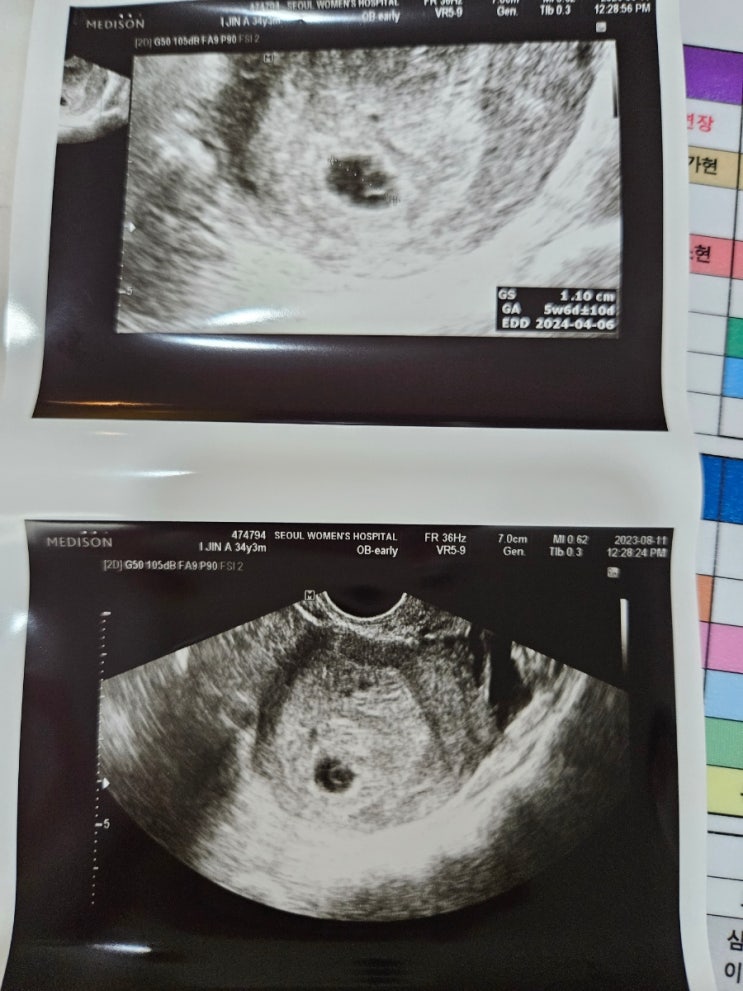

[임신7주차] 아기 심장소리 확인, 주수별 심박수

서울여성병원 산부인과 임신 7주차 아기 심장소리 듣고왔어요 나는 보건복지부가 지정한 난임전문병원인 서...